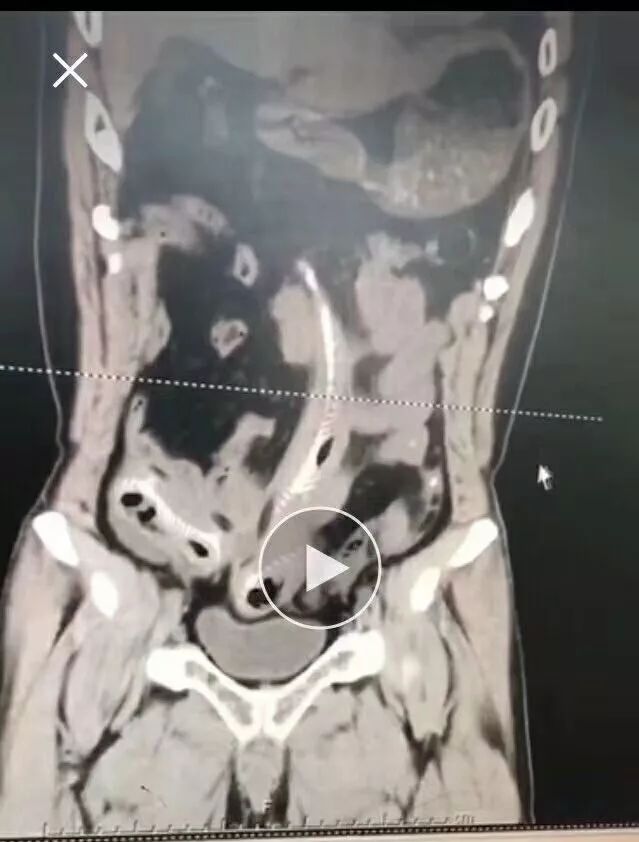

CT三维重建下三条泥鳅的骨骼清晰可见

2月10日那天我看的急诊,事情的经过是这样的,我是他的首诊大夫,一开始急诊打电话急会诊说是吃泥鳅吃坏了肚子,我觉得这也没啥,然后让他做腹部CT。后来看到他的CT赫然三条鱼骨头。我一看CT很吃惊,难道是生吃的?

去一楼急诊问患者本人,当时我听他说了事实,是下面塞进去的真把我吓一跳。他第一句话就是说,听信网上前列腺偏方把他害惨了,让我救救他赶紧手术,问我有没有穿孔,当时只有一个小时,还早,摸着板状腹很硬。他意识还有,后来就慢慢感染中毒休克了。后来术中发现乙状结肠穿孔,三条鱼都到了腹腔里,有一条还往回盲部钻,不过取出来应该都是死的了。